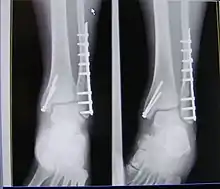

| X-ray of trimalleolar fracture repair before and after ORIF surgery | |

Surgical repair using open reduction and internal fixation is generally required, and because there is no lateral restraint of the foot, the ankle cannot bear any weight while the bone knits. This typically takes six weeks in an otherwise healthy person, but can take as much as twelve weeks. Non-surgical treatment may sometimes be considered in cases where the patient has significant health problems or where the risk of surgery may be too great.[1]